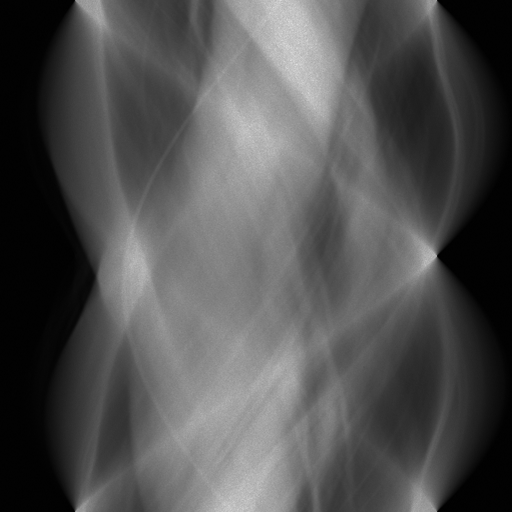

A sinogram is a 2D projection-domain representation of computed tomography (CT) data, where each row corresponds to an acquisition angle and each column to a detector position. In practical CT reconstruction pipelines, projection data are often incomplete due to limited-angle acquisition, reduced sampling, or experimental constraints, and missing sinogram measurements can introduce severe artifacts that are amplified during reconstruction (Kalender, 2011). Sinogram completion therefore plays a critical role in restoring projection data prior to image reconstruction.

High-resolution sinograms, often reaching 2048×\times2048 or beyond, naturally arise in synchrotron and nano-scale CT systems, where dense angular sampling and fine detector resolution are required to preserve quantitative accuracy. In these settings, high resolution is required to preserve measurement fidelity and ensure stable reconstruction, and aggressive resolution reduction can fundamentally alter the inverse problem and compromise downstream analysis (Slaney and Kak, 1988).